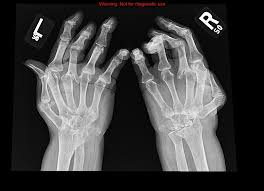

If the pattern of disease is not symmetrical, then a different diagnosis should be considered. Imaging tests you may get. The 2010 rheumatoid arthritis classification criteria help doctors diagnose rheumatoid arthritis. The ulnar styloid is destroyed with the rest of the distal ulna (white arrow), there is destruction of the carpal bones (yellow arrow) and there is dislocation of the 1st metacarpal on the destroyed trapezium. It can affect anyone of any age. Rheumatoid arthritis (ra) is a chronic autoimmune multisystemic inflammatory disease that affects many organs but predominantly attacks the synovial tissues and joints. Rheumatoid arthritis affects around 400,000 adults aged 16 and over in the uk. Rheumatoid arthritis can be difficult to diagnose because many conditions cause joint stiffness and inflammation and there's no definitive test for the condition. Ra causes pain, swelling, stiffness, and loss of function in joints. Rheumatoid arthritis is an inflammatory arthritis affecting both small and large joints in a symmetric distribution. Rheumatoid arthritis is an immune system condition, or autoimmune disorder, that causes inflammation of the lining of the joints. Rheumatoid arthritis is a chronic inflammatory disorder that can affect more than just your joints. Rheumatoid arthritis manifests as a symmetrical arthritis, most commonly affecting the hands.

If the pattern of disease is not symmetrical, then a different diagnosis should be considered. In rheumatoid arthritis, the body's immune system attacks its own healthy cells inside certain joints, leading to an inflammatory response. For more information and past images of the month, go to. However, they are not useful in the early stages of rheumatoid arthritis, before joint damage occurs. </b>rheumatoid arthritis (ra) is a polyarticular disease with bilateral and symmetric distribution. Sorptiometry should be performed to diagnose. The rheumatoid community on reddit. Rheumatoid arthritis (present for >10 years). The ulnar styloid is destroyed with the rest of the distal ulna (white arrow), there is destruction of the carpal bones (yellow arrow) and there is dislocation of the 1st metacarpal on the destroyed trapezium. Rheumatoid arthritis affects around 400,000 adults aged 16 and over in the uk. Reddit gives you the best of the internet in one place. Ra causes pain, swelling, stiffness, and loss of function in joints. The earliest manifestation of rheumatoid arthritis of the forefoot is synovitis of the mtp joints with eventual hyperextension deformity of the mtp joints including distal.

It can affect anyone of any age. </b>small joints of the feet, wrists, and hands are frequently involved by a reduction of osteoporosis; Severe rheumatoid arthritis of the wrist and hand. Rheumatoid arthritis (ra) imaging tests are used to look for signs of ra and to monitor the disease's progression. Ra causes pain, swelling, stiffness, and loss of function in joints.

It is caused when the immune system (the body's defense system) is not working properly. Rheumatoid arthritis is a chronic inflammatory disorder that can affect more than just your joints. Rheumatoid arthritis is an immune system condition, or autoimmune disorder, that causes inflammation of the lining of the joints. Rheumatoid arthritis (ra) imaging tests are used to look for signs of ra and to monitor the disease's progression. For more information and past images of the month, go to. Reddit gives you the best of the internet in one place. These tests primarily look for bone damage in the patient's joints caused by the inflammation associated with ra. Rheumatoid arthritis manifests as a symmetrical arthritis, most commonly affecting the hands. Rheumatoid arthritis can be difficult to diagnose in its early stages because the early signs and symptoms mimic those of many other diseases. Ra causes pain, swelling, stiffness, and loss of function in joints. Rheumatoid arthritis is considered an indication for resurfacing of the patella during total knee arthroplasty. Imaging tests you may get. It can get worse quickly, so early these can be used to diagnose rheumatoid arthritis and check how the condition is developing.